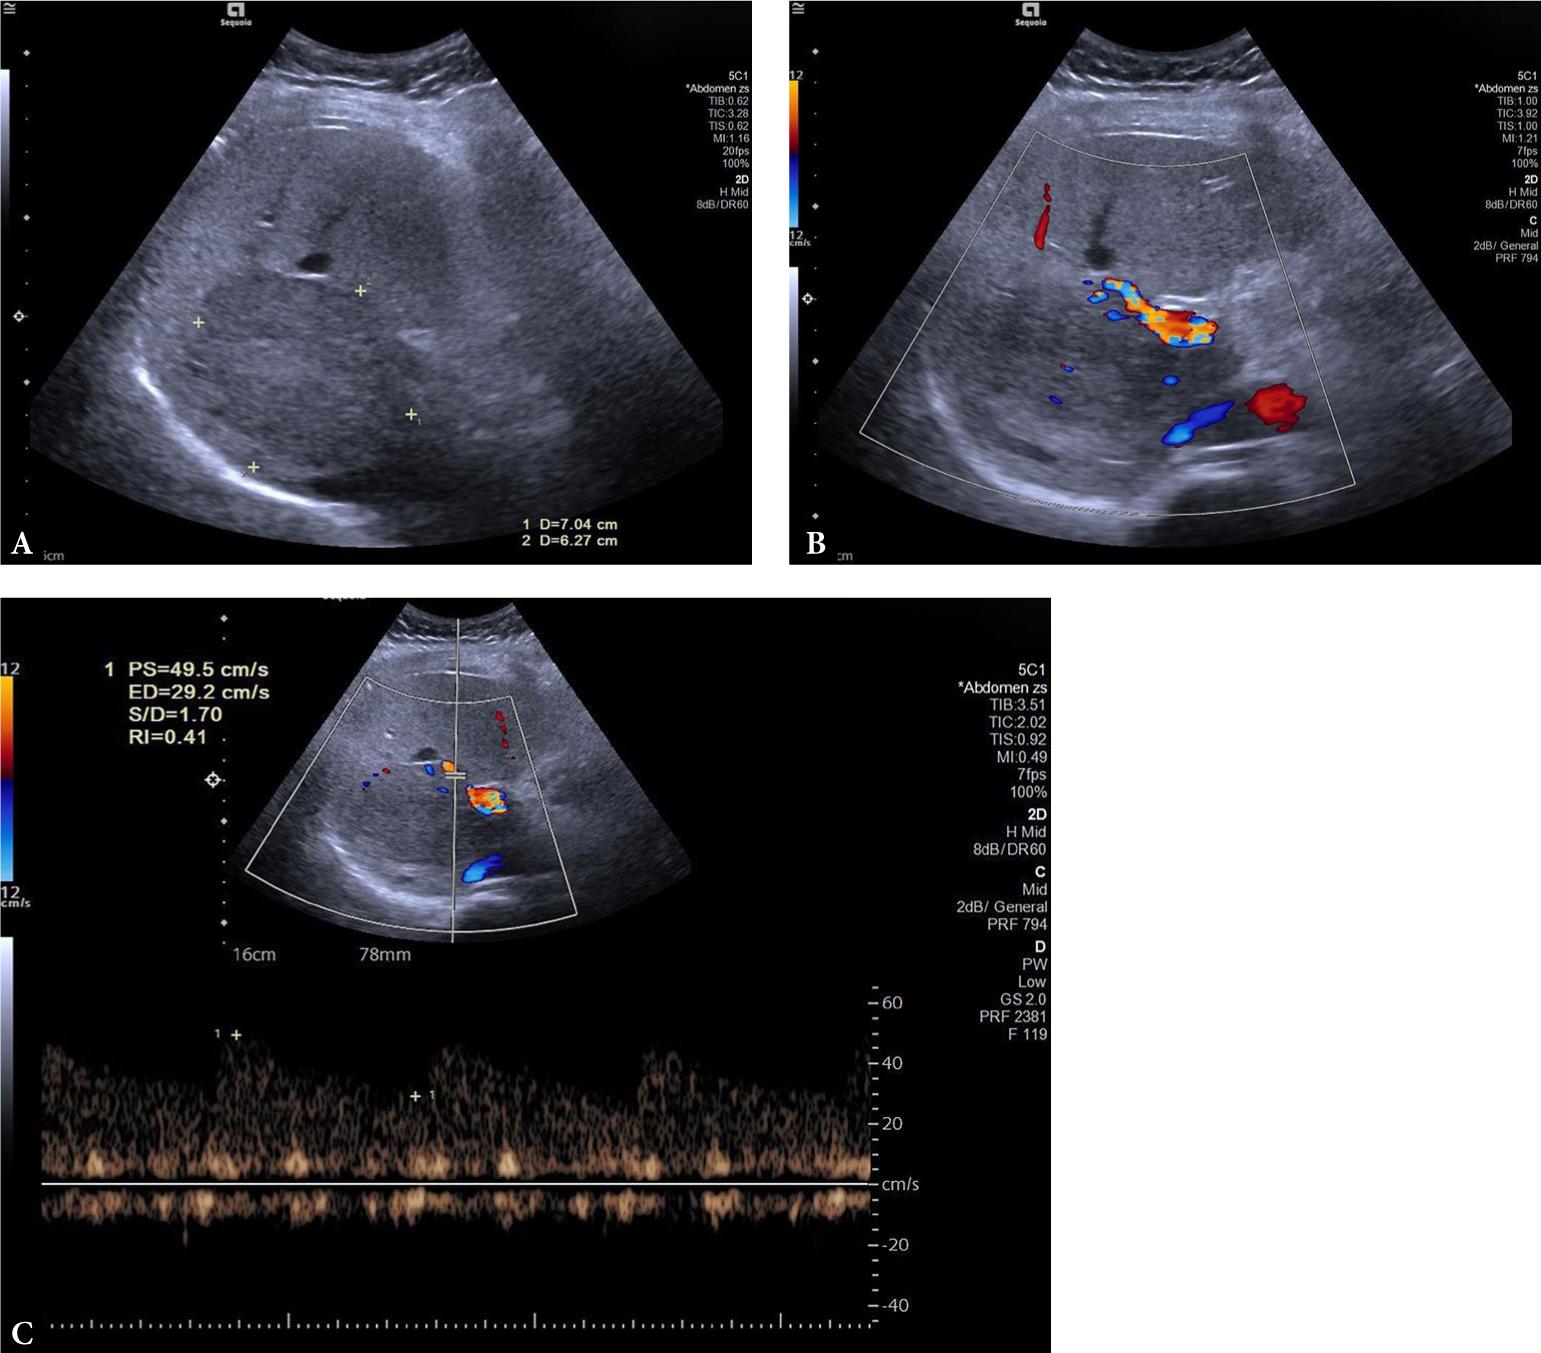

Fig. 2.